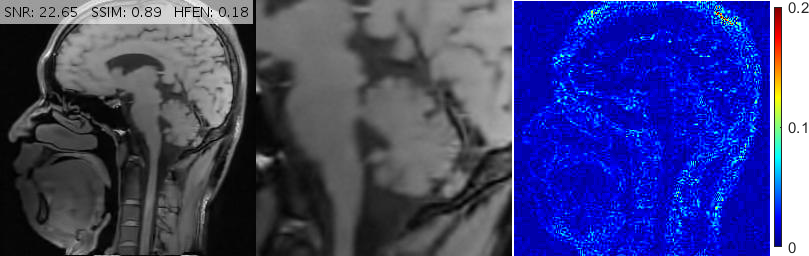

Fig. 6 depicts the reconstruction results for above setups. As attested by the magnified views and error metrics inserted to the top of each reconstruction, TV and TGV significantly degrade the reconstructed image in the rotated setup while RITV gives a remarkably consistent and high-quality result which is hardly distinguishable from the upright solution (note that HFEN and SSIM indices do not change in RITV after rotation). Of course, the upright and rotated directions are only chosen relatively and can always be swapped, nevertheless, the point is TV and TGV fail in at least one of the orientations while RITV succeeds in both. Note that if the selected MR image and Cartesian mask are denoted by and respectively, then a simple machine-aided computation shows that . Therefore, even though the norm-preserving assumption of Theorem 2.1 does not hold true in this experiment (and in fact in many practical situations), the result of RITV is still incredibly isotropic.

Fig. 10 shows the performance of various algorithms for a sagittal head scan reconstruction under 16% spiral sampling. The solutions provided by pFISTA and TL miss much of the image content due to over-smoothing. TGV+Shearlet leaves many incoherent artifacts on all regions. The magnified views obviously show that BM3D degrades the image by leaving block artifacts around the cerebellum and streaking artifacts on the medulla and the visual cortex. DAMP, GBRWT, ADMM Net and FDLCP provide more accurate results, however, by inspecting the magnified views it becomes evident that some small artifacts are introduced in DAMP near the caudate nucleus and beneath the cerebellum while a dark hole at the center of the cerebellum has been almost entirely smoothed out by the other three methods. The proposed method (labeled ‘New’) accurately captures this hole and corrects all the errors mentioned above.

For convenience, in Figs. 10, 11 and 13 we have inserted the SNR, SSIM and HFEN values for each method to the top of the corresponding reconstructed image. Moreover, some reconstruction errors in compared methods and their corrections in the proposed method are annotated with arrows.